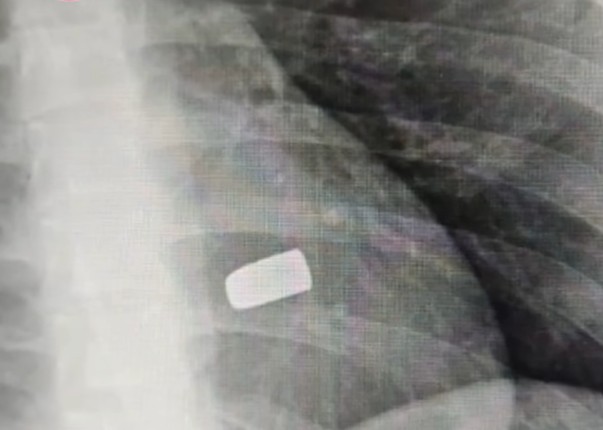

Deivid foi levado para o Hospital Lázaro Mendes, mas morreu minutos depois de chegar ao local. Ele foi atingido no coração e no abdômen e teve vários órgãos perfurados.